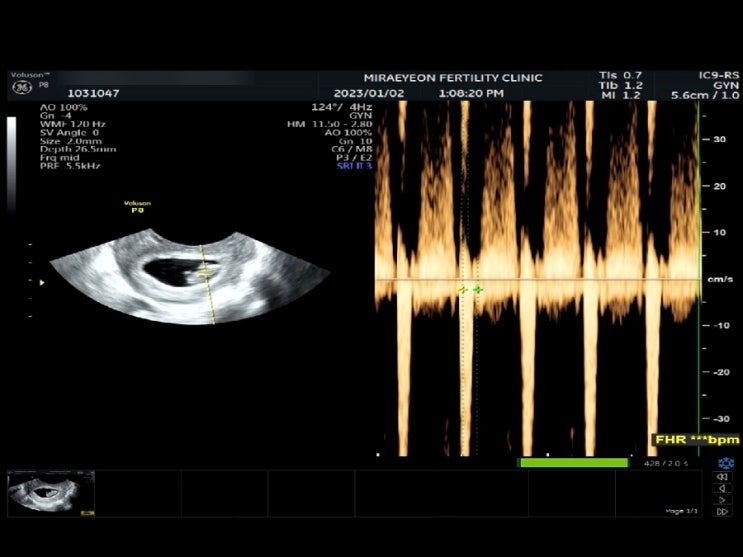

[7주6일] 심장소리 들은 날 ,젤리곰 확인 (feat. 영화데이트:아바타2)

2023.01.02 오늘은 "첫 심장소리"를 듣는 날입니다. 2주 전 초음파를 처음 봤을 당시 콩알같이 ...